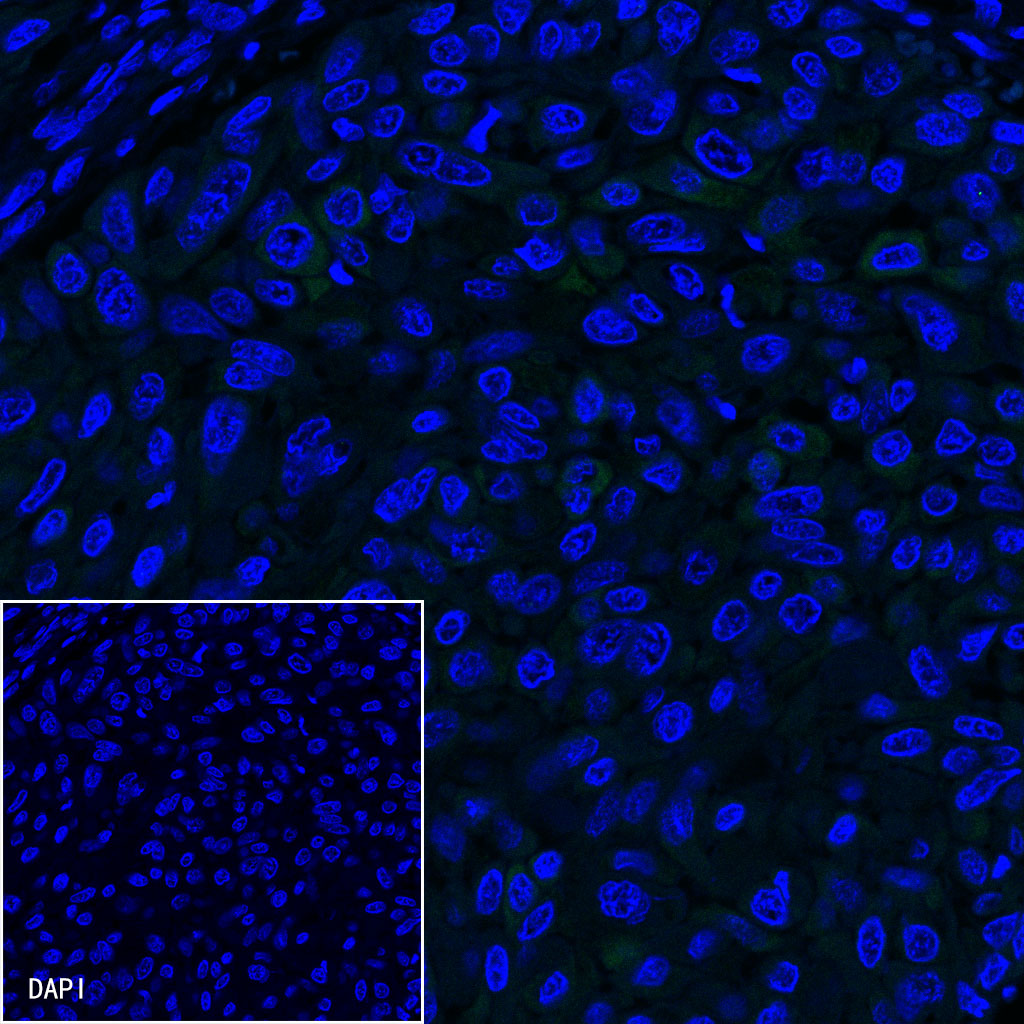

| IF |

1:500 |

Background

CK-LMW is low molecular weight cytokeratins and is expressed in monolayer or glandular epithelium of normal or tumor tissues, such as thyroid, breast, gastrointestinal or respiratory epithelium. It is expressed in adenocarcinoma and the vast majority of nonkeratinizing squamous cell carcinoma, but not in keratinizing squamous cell carcinoma. It combined with CK5/6 for diagnosis of adenocarcinoma and squamous carcinoma.